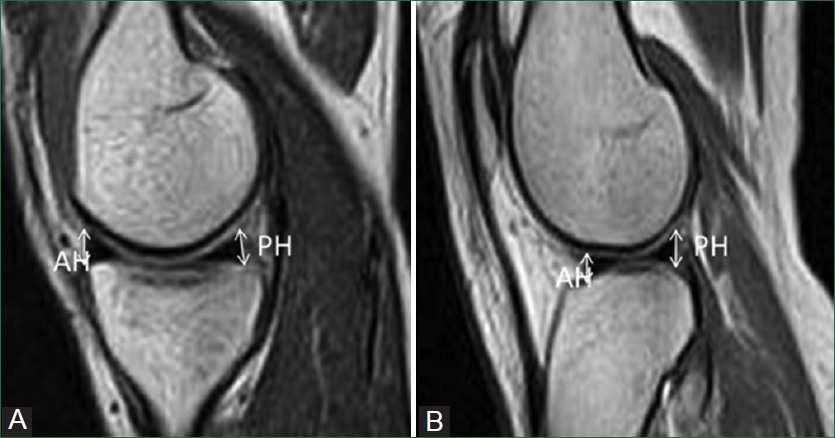

Background: Since the in vivo morphometric data on the menisci of the knee joint of Indian subjects are scarce, we hereby studied the width and thickness of the menisci using Magnetic Resonance Imaging (MRI) to establish standard dimensions of the normal medial and lateral meniscus as an aid to orthopaedic surgery.

Methods: Eighty menisci from 40 knee joints were analysed in each of three regions, the anterior horn, the mid body and the posterior horn. The thickness and width of the menisci were measured in sagittal and coronal T1-weighted and T2-weighted MRI images and analysed statistically.

Results: The mean thickness of medial meniscus at the anterior horn, mid body, and posterior horn were 6.3 ± 1.1 mm, 5.2 ± 1.3 mm, and 6.9 ± 1.1 mm, respectively. The respective values for the lateral meniscus were 4.8 ± 0.7 mm, 6.4 ± 1.1 mm, and 7.0 ± 0.9 mm. The mean width of medial meniscus at the anterior horn, mid body, and posterior horn were 10.5 ± 1.2 mm, 7.8 ± 1 mm and 13.9 ± 0.9 mm, respectively. The widths of lateral meniscus at the same regions were 11.8 ± 1.4 mm, 8.6 ± 1.2 mm, and 12.0 ± 0.9 mm, respectively. The lateral meniscus was significantly wider than medial at the anterior horn and mid body (p = 0.00). In contrast, the posterior horn of medial meniscus was significantly wider than lateral meniscus. Both menisci were significantly wider at their posterior horn, followed by the anterior horn and were significantly narrower at their mid body.

Conclusion: The present study provides new information on the meniscal thickness and width in South Indians that can be used in planning of orthopaedic and arthroscopic surgeries of the knee joint. However, the study needs to be analyzed with a large sample size for the better interpretation.